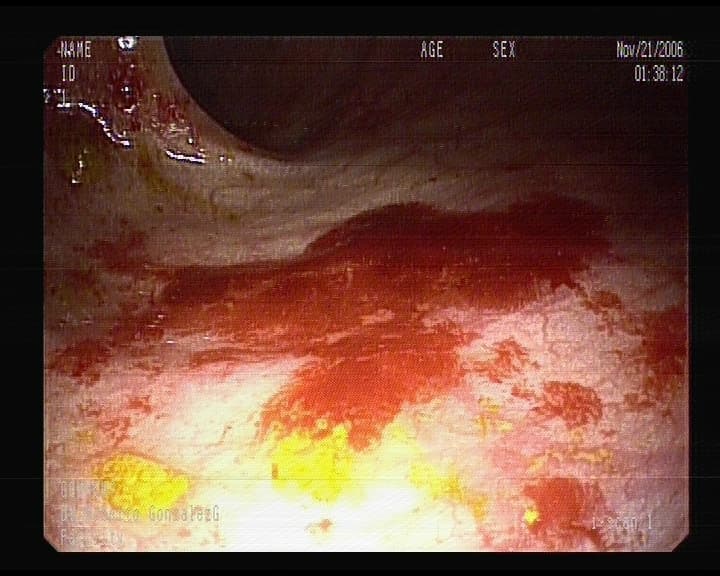

Estómago por ingesta de Caústicos

Lesiones hemorrágicas producidas por Ingesta de cáusticos.- Quemaduras-.